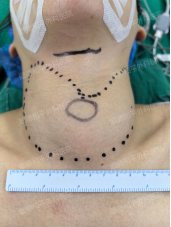

患者术前&术后颈部对比

术后,吴路杨主任耐心叮嘱患者:需坚持服用甲减药物,前期每月复查,病情稳定后调整为每三个月复查一次。虽然存在复发可能,但几率已大幅降低。如今,术后第5天,患者康复情况良好,可见颈部情况已与正常无异,无裸露切口,精神面貌焕然一新,她还表示对治疗效果非常满意,可以放心出院回家了。